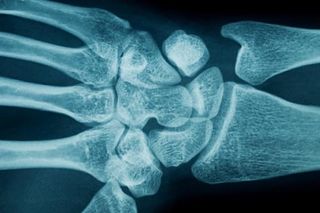

Carpal tunnel syndrome occurs when the carpal tunnel — a narrow, rigid channel comprising bone and ligaments that runs along the underside of the wrist — collapses or narrows, squeezing the median nerve, which runs through it, according to the U.S. National Institute of Neurological Disorders and Stroke (NINDS). The median nerve runs from the forearm to the hand, where it controls some movement and touch sensations. When the median nerve is compressed, hand strength and sensation may be compromised and pain is common.

Carpal tunnel syndrome is most commonly diagnosed between the ages of 30 and 60. Doctors typically take a medical history; a physical examination of sensation, strength, and reflexes; and a diagnostic test such as an X-ray or tests of how well nerve impulses are reaching the related muscles, according to the American Association of Neurological Surgeons.